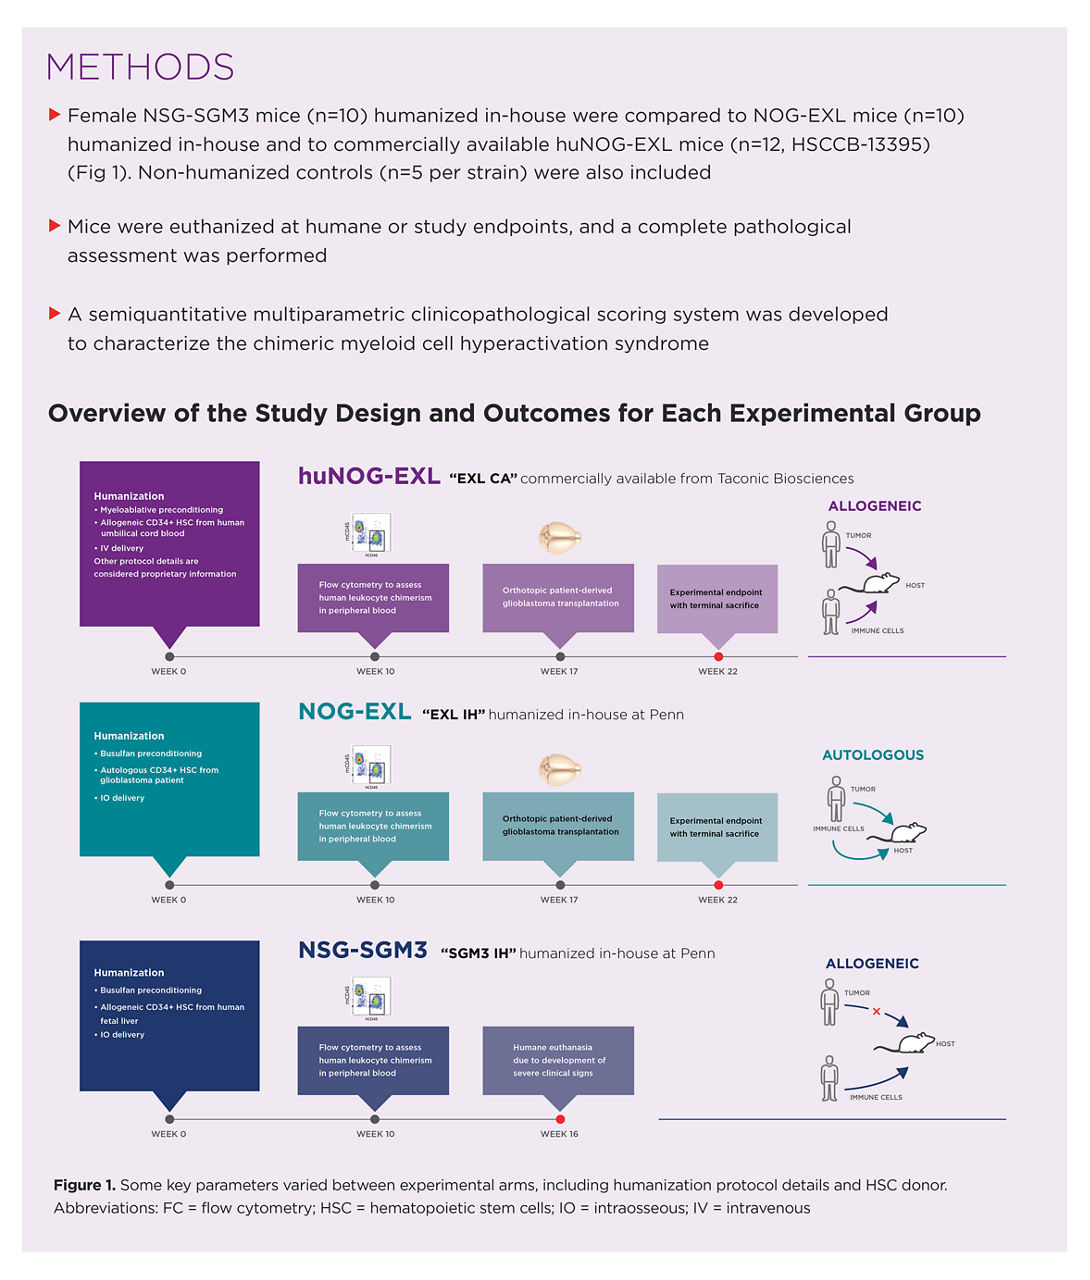

NOG-EXL mouse model from Taconic outperforms NSG-SGM3 in new

NOG-EXL mouse model from Taconic outperforms NSG-SGM3 in new

NOG-EXL mouse model from Taconic outperforms NSG-SGM3 in new,

NOG-EXL mouse model from Taconic outperforms NSG-SGM3 in new, NOG-EXL mouse model from Taconic outperforms NSG-SGM3 in new,

NOG-EXL mouse model from Taconic outperforms NSG-SGM3 in new, CIEA NOG mouse® | Taconic Biosciences,